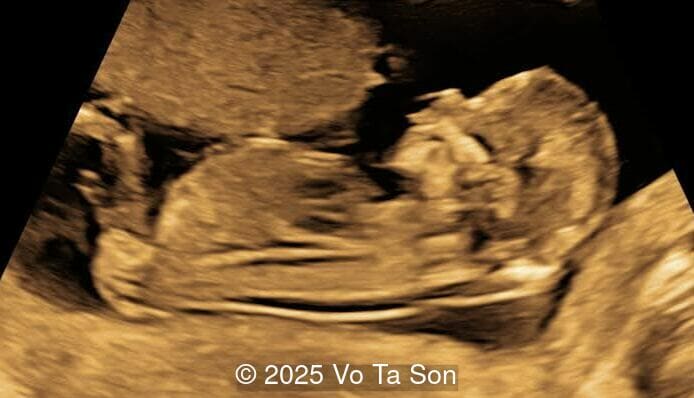

3D Image

Image 2 3D Image

Spinal defect in the sacral region visualized on 3D ultrasound.

Image 3 Spinal defect in the sacral region visualized on 3D ultrasound.

Image 4 Spinal defect in the sacral region visualized on 3D ultrasound.